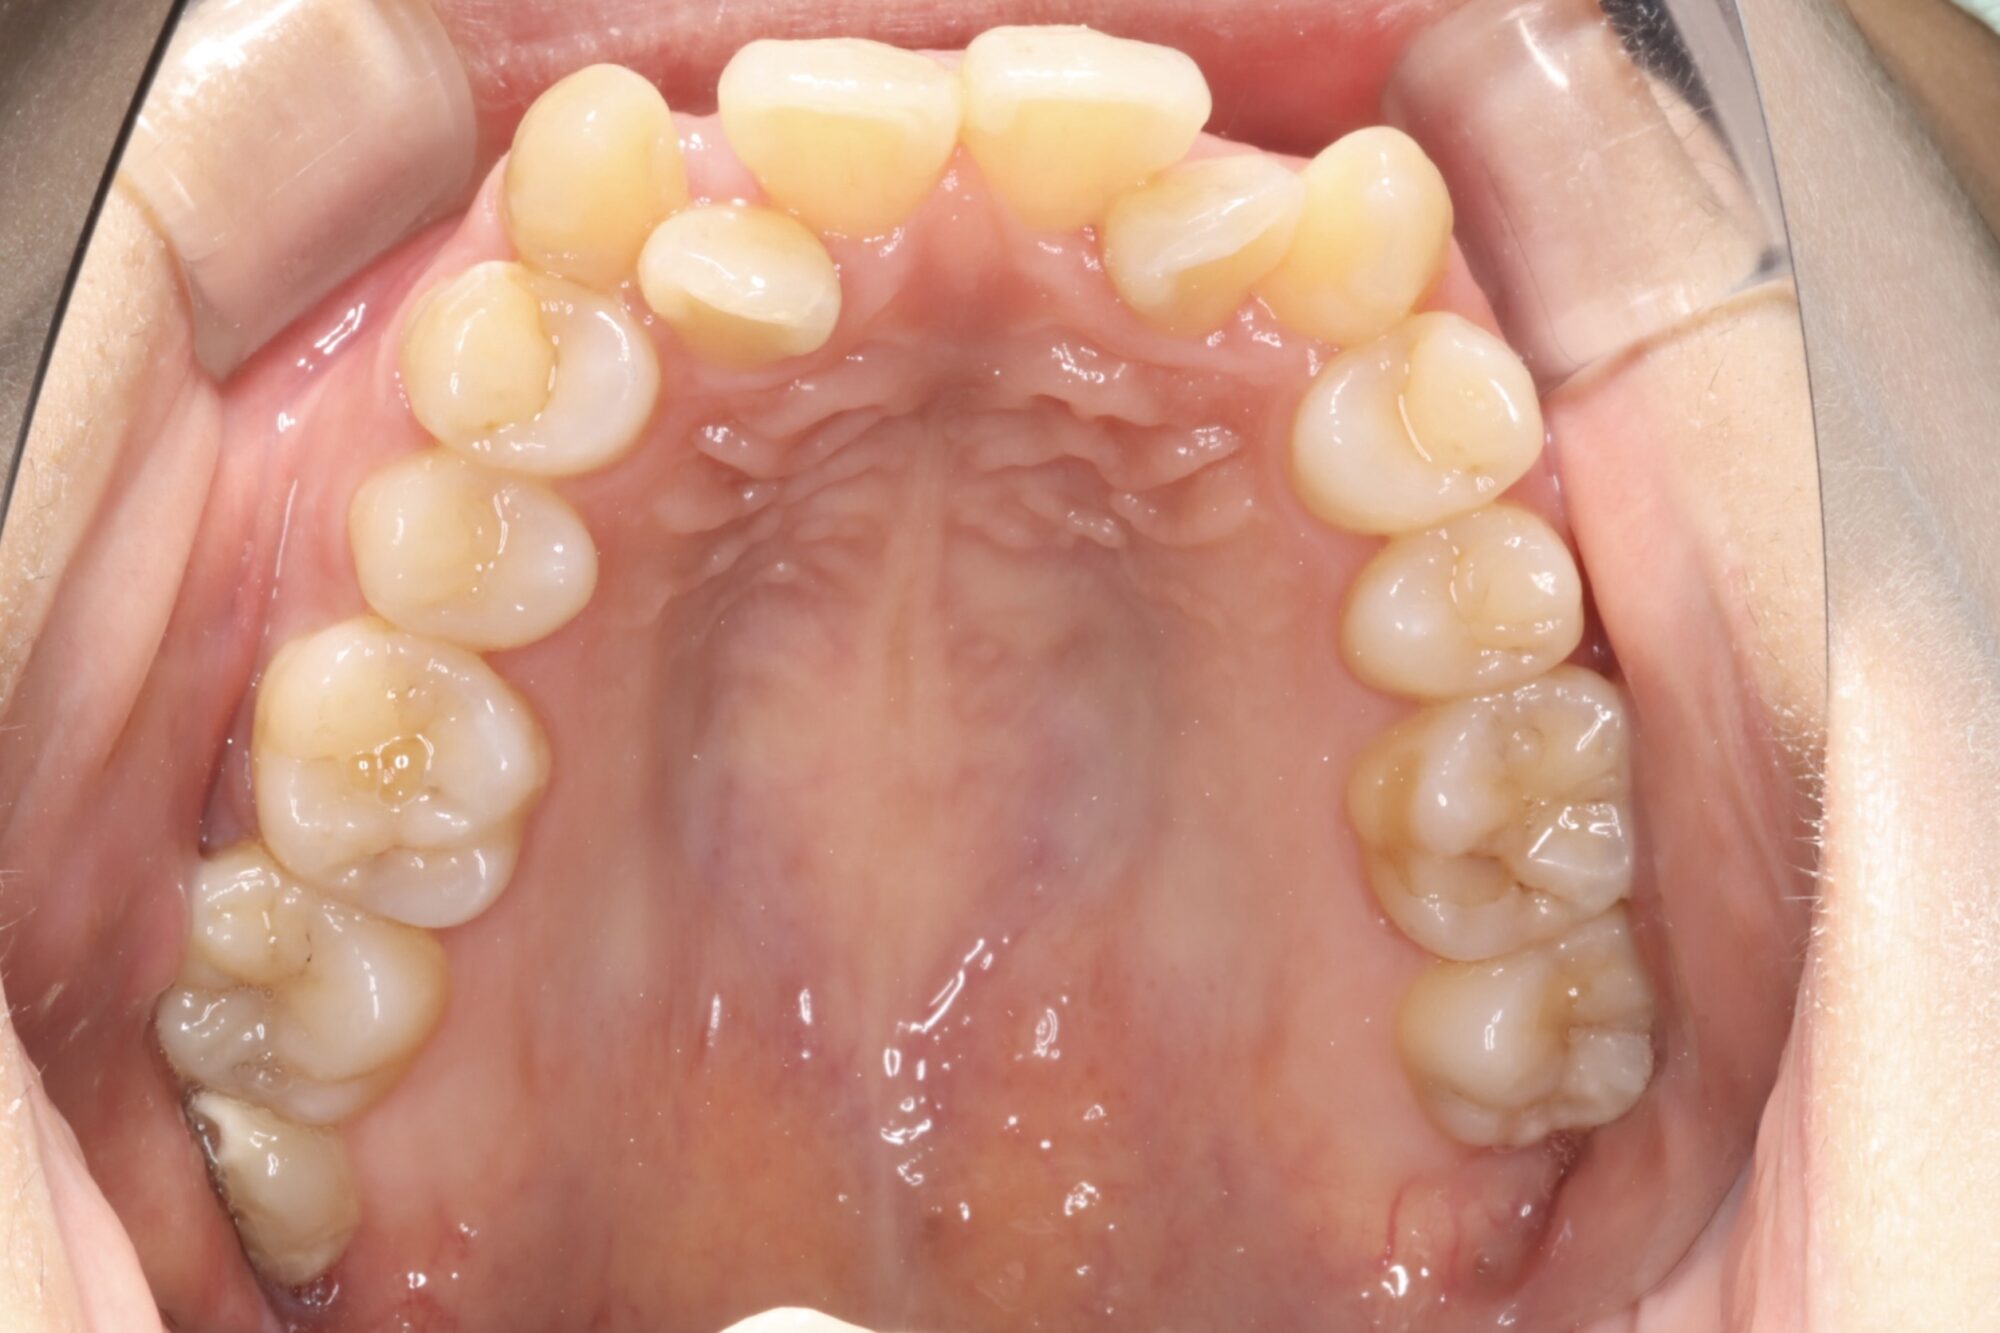

写真は矯正治療を始める前です。